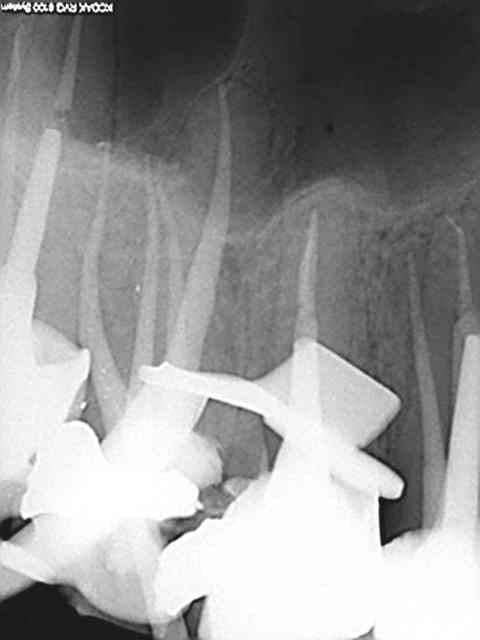

Bien sûr il y a des loupés, et des vedettes (voir illustrations plus haut). Maintenant si on est extrême au point de penser que toute endo faite sans digue condamne la dent à la poubelle, c'est difficile de discuter.